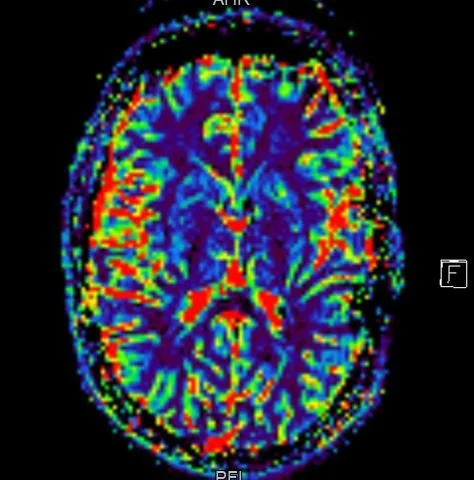

Rare and pediatric disease trials come with complex challenges that require specific expertise and experience. We have the radiology exerts to support the specific requirements of pediatric clinical trials. Many rare diseases affect children, and pediatric trials bring additional challenges.

They require specific protocols, involve additional regulations and demand expertise and experience. BICL’s experts are experienced in oncology, MSK and other pediatric disorders including growth plate disturbance, bone age and osteochondroma.